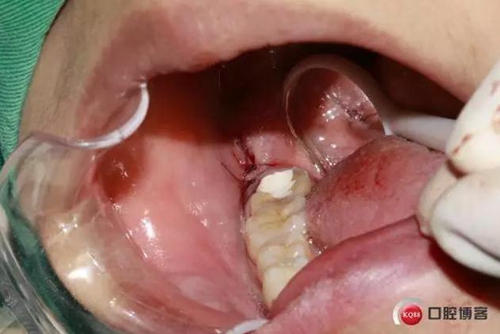

拔牙創(chuàng)口,清理周邊肉芽,切忌,不能搔刮。

縫合。